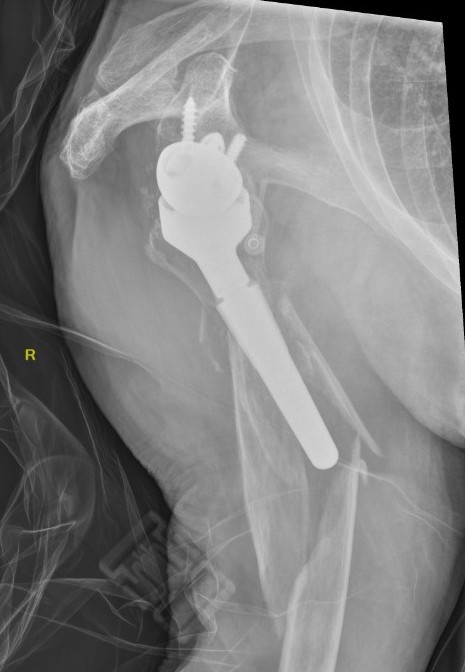

Failed Glenoid Reverse TSRReverse TSR Loose Metaglene

Loose metaglene

Lysis around humeral and glenoid component